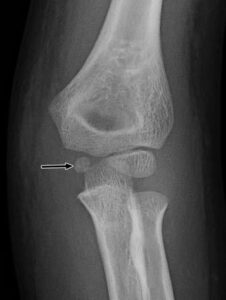

[toggle title=”Radiokapitellar Hat” state=”close”]

AP, Lateral ve Oblik grafilerde radius başının ortasından geçecek şekilde çekilen çizgi kapitulumun ortasından geçmelidir.

Bu hat üzerinde herhangi bir sapma radius başı çıkığını düşündürür. Bunun dışında lateral kondil kırıklarında da bu hat üzerinde bozulma görülebilir.

Radiokapitellar Hat Kapitulumun medialinde kalmış